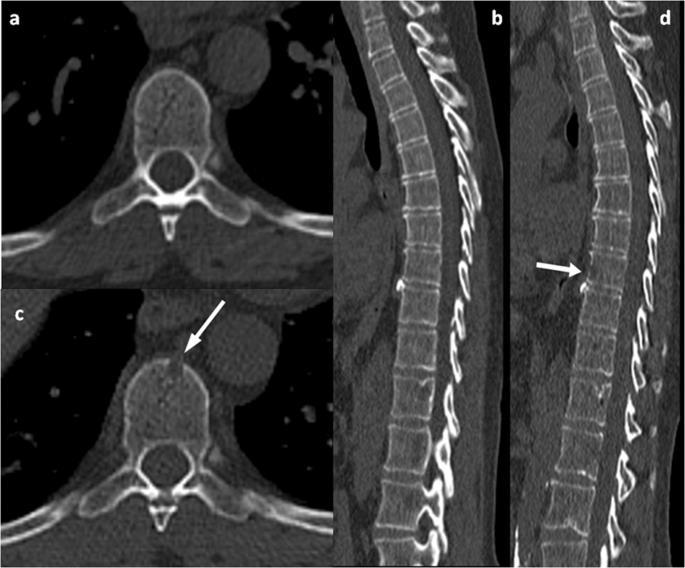

Imaging for Multiple Myeloma

SEVERAL OPTIONS FOR BONE IMAGING

Whole Body

Low-Dose CT (WBLDCT)

Best for early screening for bone disease

PET/CT

Response assessment: active residual disease

MRI

Whole body (WB) or spine + pelvis

Gold standard to assess bone

Image: Gavriatopoulou M, et al. Blood Cancer J. 2020;10:93

marrow involvement

CT = computed tomography; DEXA = dual-energy x-ray absorptiometry; MM = multiple myeloma; MRI = magnetic resonance imaging; PET = positron emission tomography; WB = whole body; WBLDCT = whole-body low-dose computed tomography. Brigle K, et al. J Adv Pract Oncol. 2022;13(suppl 4):7-14. Hillengass J, et al. Lancet Oncol. 2019;20(6):e302-e312. Rome SI, et al. Clin J Oncol Nurs. 2017;21(5 suppl):47-59. Faiman B. Clin Lymphoma Myeloma Leuk. 2014;14:436-440. Dimopoulous M, et al. Leukemia. 2009;23(9):1545-1556.

NOTE: Bone scan (DEXA) for bone density is not for MM